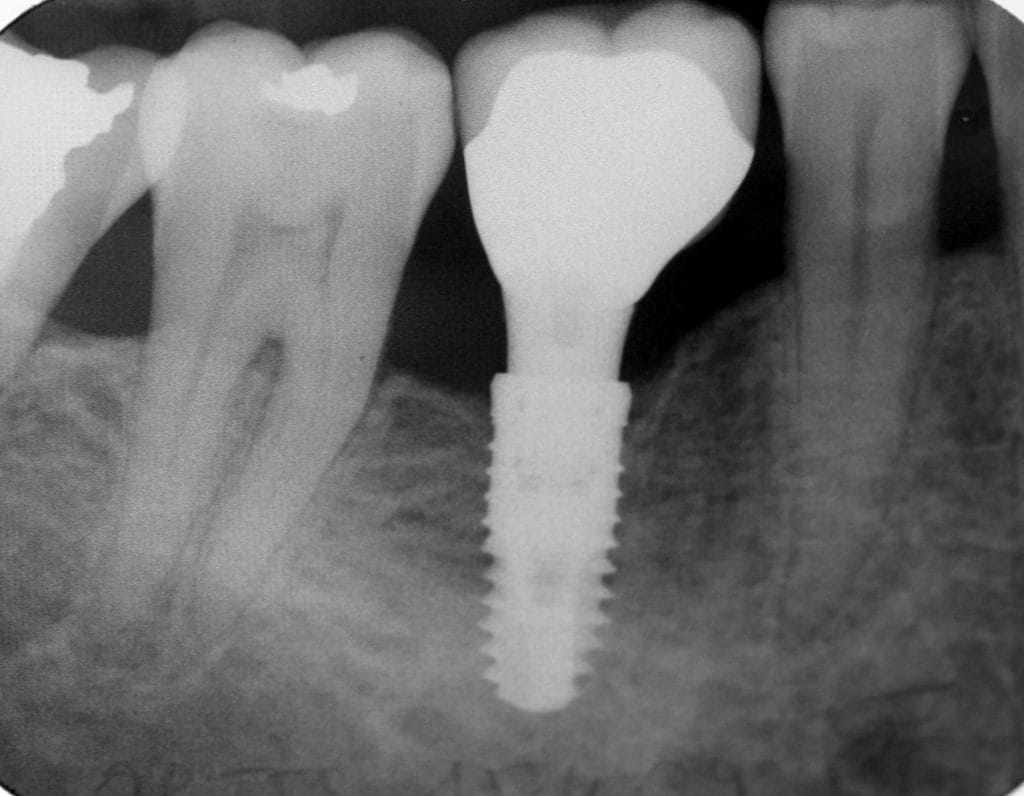

Si vous ne faites rien les dents voisines voudront bouger pour combler le vide laissé par la dent extraite. C’est alors qu’il faudra poser un implant dentaire pour retrouver :

- une fonction de mastication

- un confort au quotidien

- une esthétique dentaire.